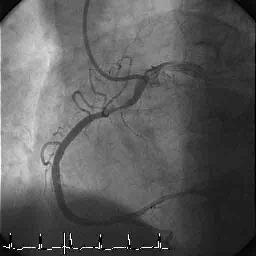

症例のご相談をいたします。症例は60才男性で1990年にUAPにてSVG to RCA SVG to

Lcxの2枝CABGを施行されている方です。Riskは高血圧です。川崎病なし、FHなしです。

術後12年間は胸痛なく、Ca拮抗剤にて血圧も安定しておりました。2002年9月ころよ

り安静時の胸部不快感を自覚されたために10月1日にCAGを施行いたしました。(TBA)

結果、#1 100% #13 100% SVG to RCA patent SVG to Lcx patentでありましたがLAD

に冠動脈瘤を認めました。また#7に75%狭窄を認めます。LAD flowは瘤+狭窄のた

めdelayとなっております。心臓血管外科がいないということもありIVUSをしようと

したら周囲に止められましてIVUSは施行しておりません。

アンギオのLAD-2の方を見れば瘤の中にLADがある程度重なって濃く見えるように

思われます。静止画だけなので不確実ですが開口部はそれ程長くないのではない

か、と思われます。